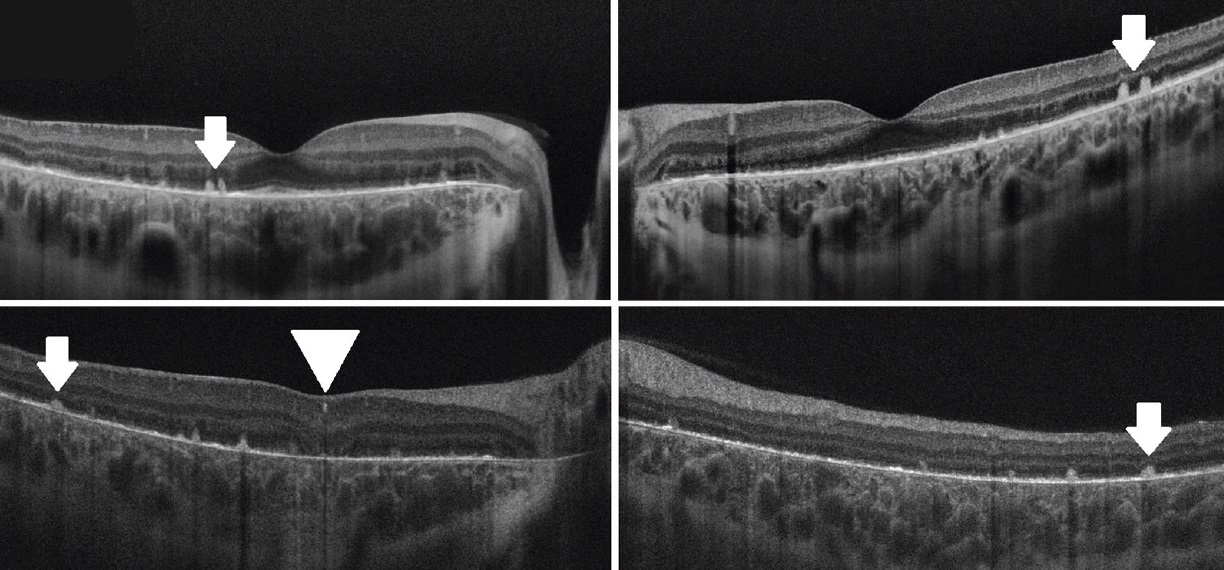

Оптична-когерентна томографія (ОCT) виявила плями гіперрефлексії (рис. 3, біла стрілка) у внутрішніх шарах сітківки, яскраві світловідбиваючі відкладення (біла стрілка) зверху пігментного епітелію сітківки (RPE) – на мембрані Бруха та відсутність зовнішніх канальців сітківки в кожному оці. Порушення еліпсоїдної зони та пігментного епітелію сітківки було більш помітним на парафовеальних зрізах ОCТ. Наявність помітних кристалічних відкладень на сітківці разом із результатами FAF та ОCТ привели до рішення, що діагнозом є рання стадія кристалічної дистрофії Б’єтті (BCD).

Рисунок 3.